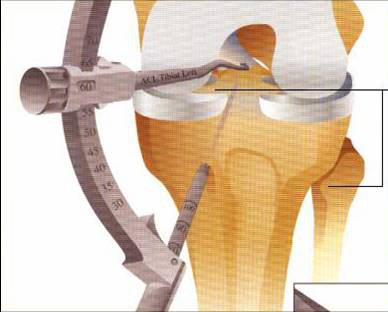

脛骨點選取

股骨點

Rigidfix固定

Intrafix固定